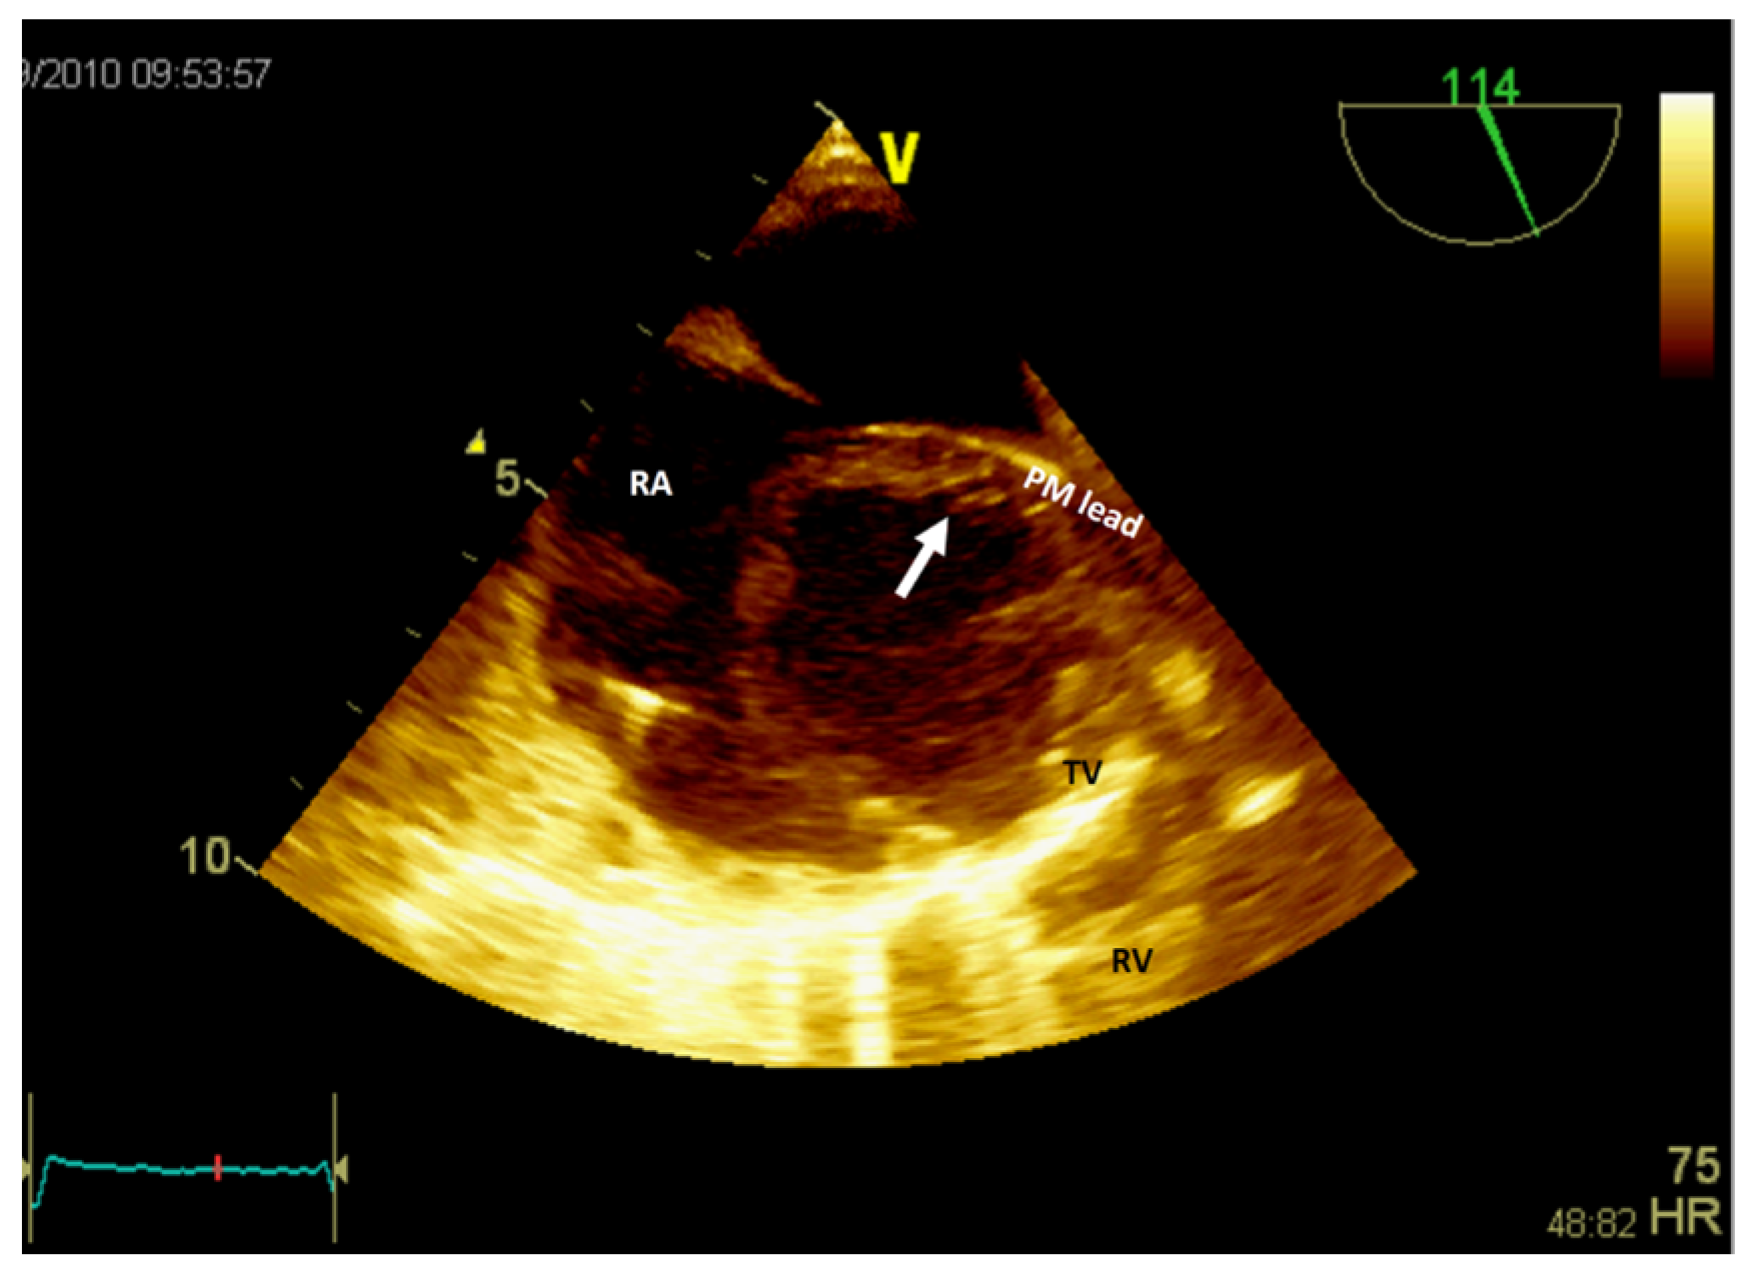

- Grecu, M.; Floria, M.; Tinică, G. Complication due to entrapment in the Chiari apparatus. Eur. Eur. Pacing Arrhythm. Card. Electrophysiol. J. Work. Groups Card. Pacing Arrhythm. Card. Cell. Electrophysiol. Eur. Soc. Cardiol. 2014, 16, 577. [Google Scholar] [CrossRef] [PubMed]